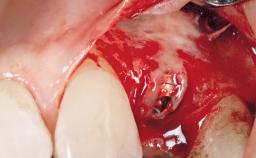

Type of Implants One-Piece

Placement Protocol Immediate implant placement

Socket Morphology Single-root socket

Socket Integrity Damage to one or more bone walls

Bone Volume Damage to one or more socket walls